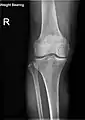

X-ray

Knee X-ray

Knee X-ray (weight bearing)

Knee X-ray (weight bearing, flexion)